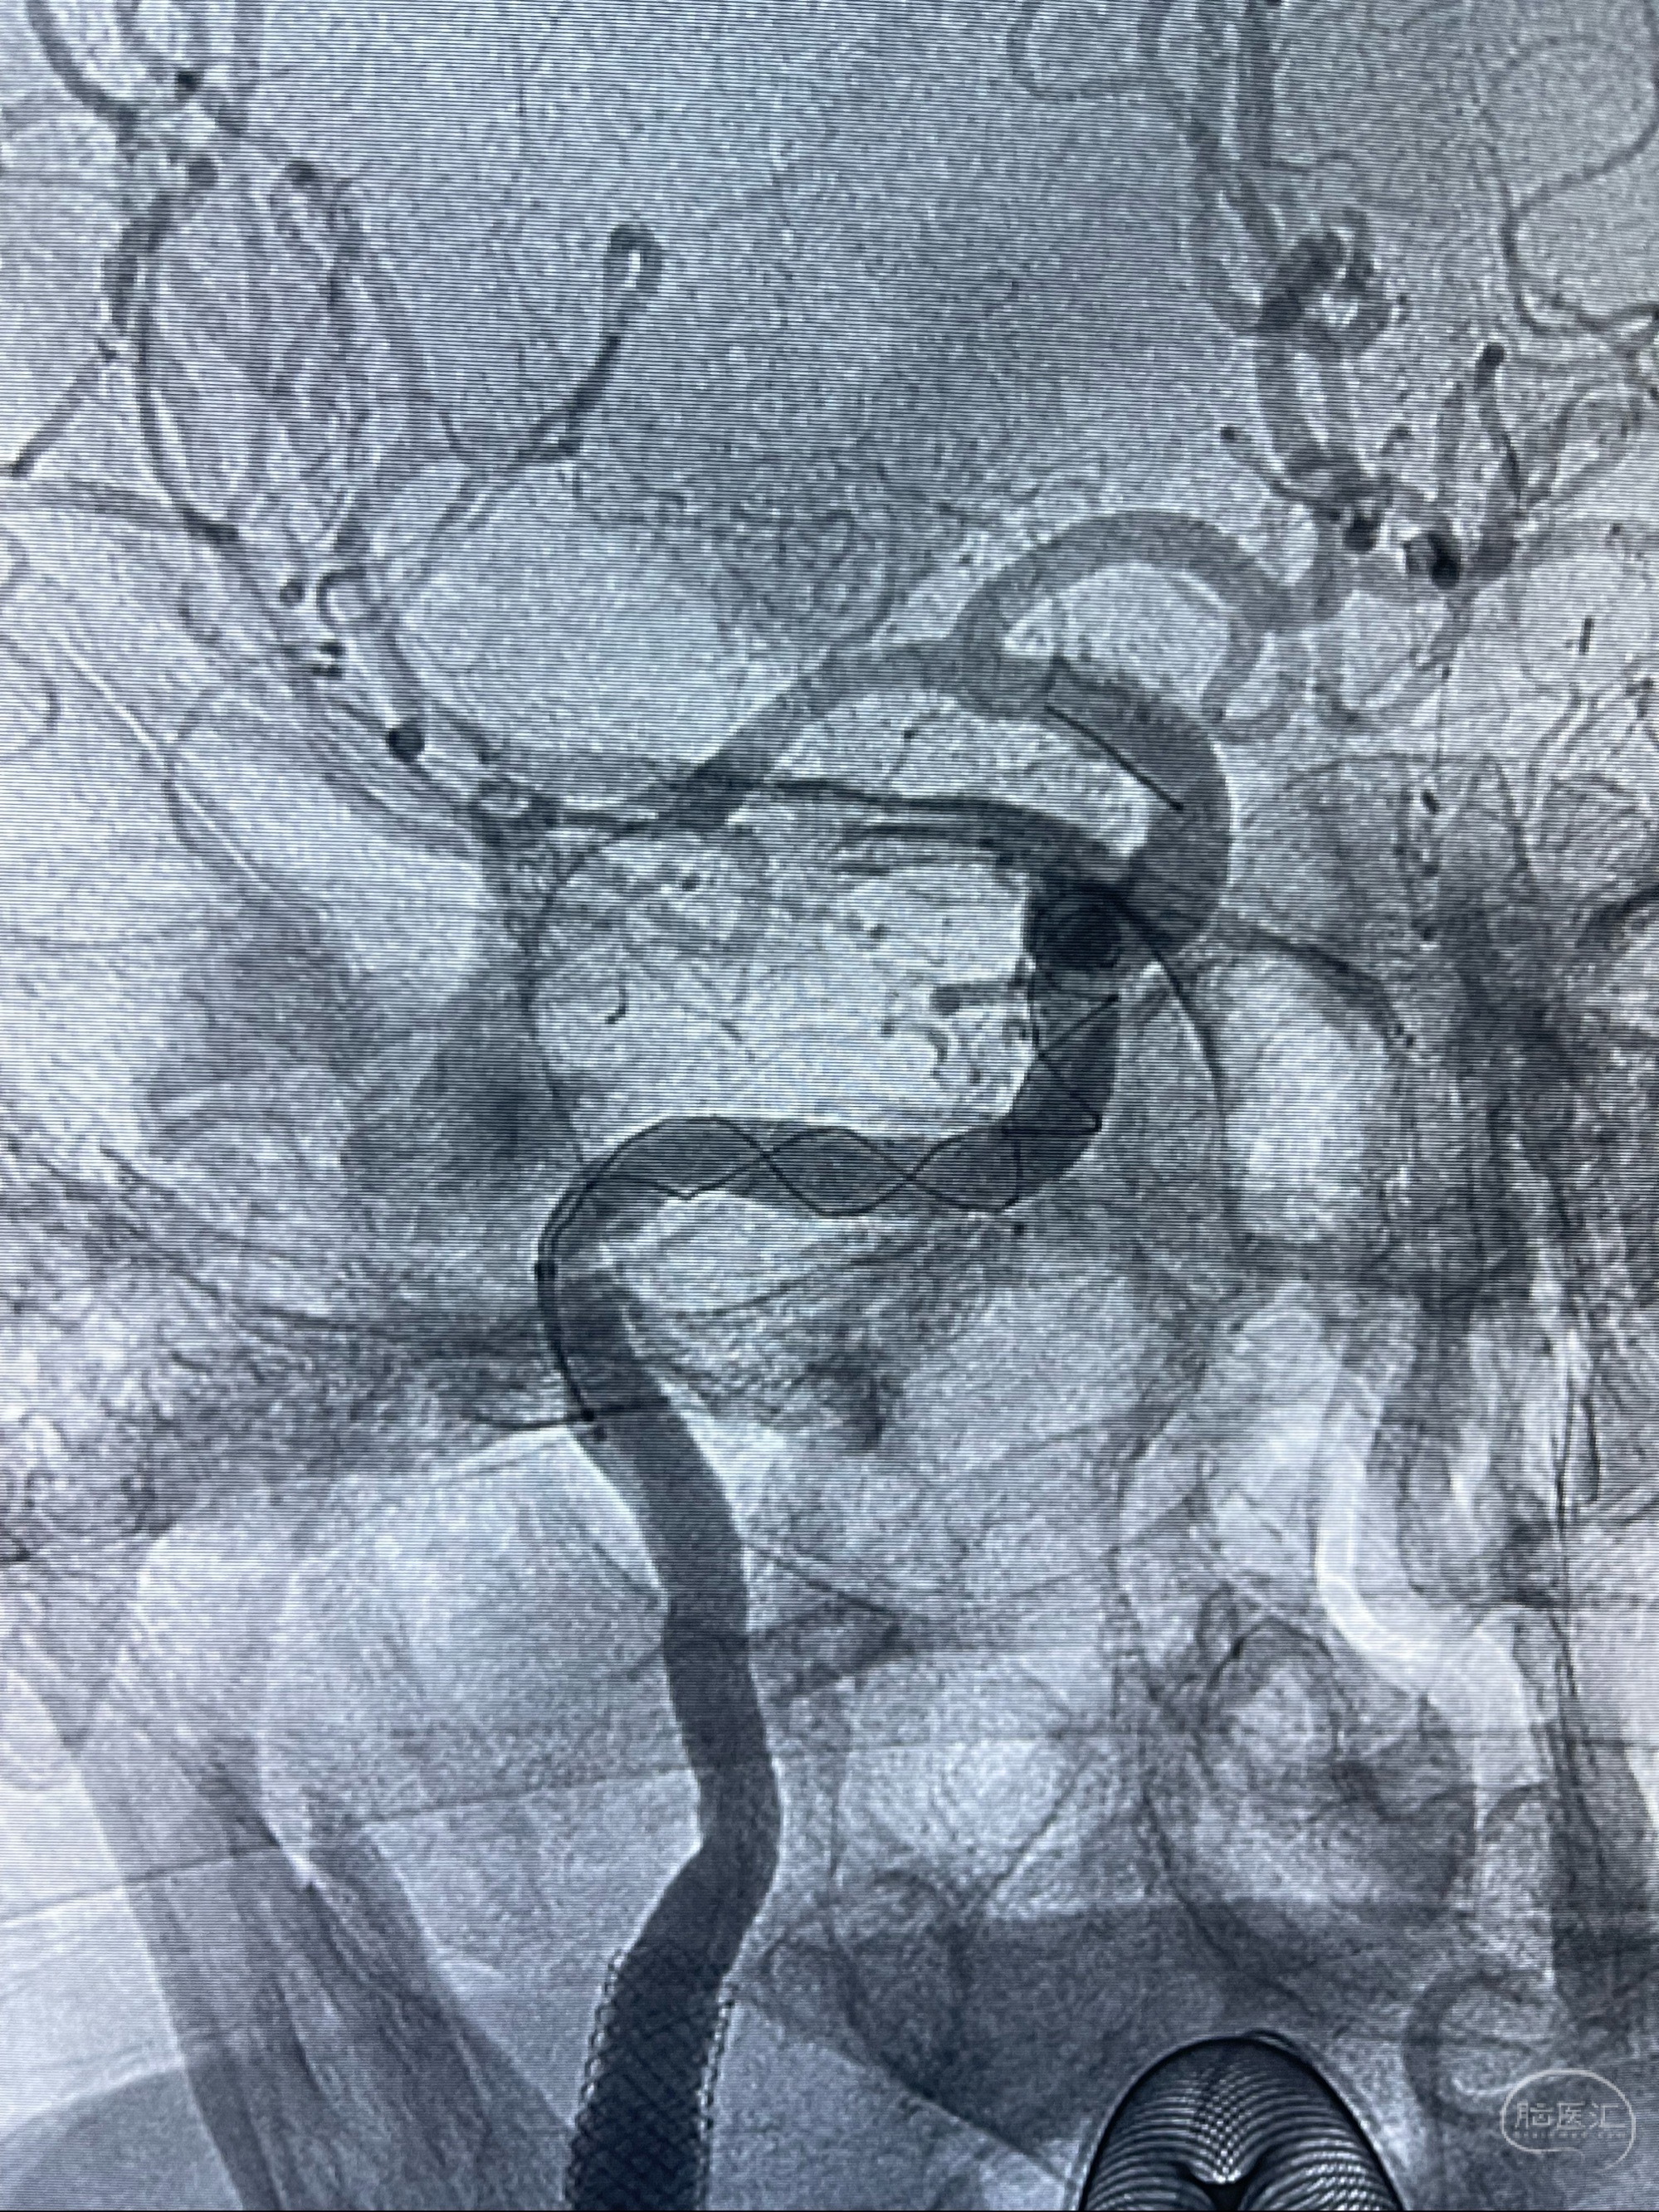

2023-07-10DSA:右侧颈内动脉岩骨段夹层伴中偏重度狭窄改变,左侧颈总动脉闭塞、右侧颈外动脉由右侧肋颈干甲颈干吻合代偿

箭头所示为颈内动脉岩骨段重度狭窄,结合MRI,考虑为肿瘤侵犯右侧颈内动脉

箭头以近至支架段管腔不规则狭窄

双抗准备后于2023-07-13在全麻下行右侧颈内动脉功能保护

088NeuroMAX100cm长鞘在125cmMPA及黑泥鳅导丝引导下超选择性插入右侧颈内动脉支架内

经导引导管造影显示支架远端颈内动脉不规则狭窄伴局部充盈缺损,同时行全身肝素化5ml

路径图下4-20mm球囊在导丝引导下超选择性至狭窄段,以6-8个大气压扩张,持续30s

泄除球囊造影显示局部管腔扩张佳

后移球囊至颈段狭窄段,以8-12个大气压扩张,持续30s后泄除球囊

即刻造影显示狭窄扩张佳

重新行“路径图”,支架导管在微导丝引导下超选择性插入至右侧颈内动脉眼段,4.5-50mmLeo支架释放,远心端位于海绵窦段,近心端位于岩骨段狭窄段以近

即刻造影显示支架贴壁佳

路径图下,5.5-50mmLeo支架导管在微导丝引导下超选择性插入远段Leo支架内

两枚支架部分重叠

多次确认支架位置及打开贴壁情况

支架完全打开,近心端位于原颈动脉支架远心端内